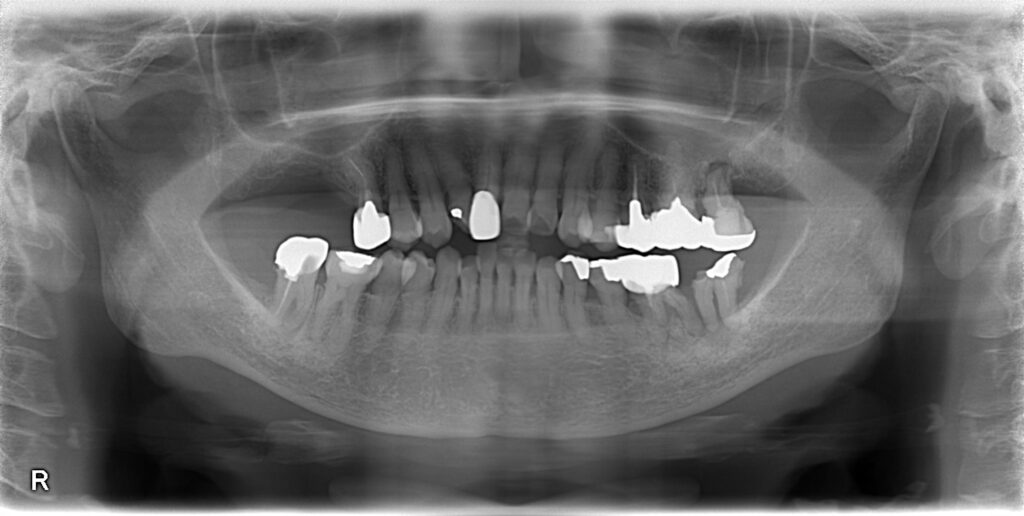

パノラマレントゲン写真です。

右と左が逆に撮影されるので、画像の右が、患者さんの言う左、画像の左が、患者さんの言う右、になります。

もう一度レントゲンを見て、果たしてインプラント治療をどう考えるか、は最終的には患者さんがお決めになることです。